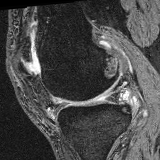

Moving Target Mono-0 Mono-5 DA-1 DA-5 Mono-200 Refer to caption Refer to caption Refer to caption Refer to caption Refer to caption Refer to caption Refer to caption Refer to caption Refer to caption Refer to caption Refer to caption Refer to caption Refer to caption Refer to caption

Figure 2:  Examples of knee MRI registration (top) and brain MRI segmentation (bottom) results. Top: The first two columns are the moving image/segmentation and the target image/segmentation followed by the warped moving images (with deformation grids)/segmentations by different models. Bottom left to right: original image, manual segmentation, and predictions of various models. Mono-i𝑖i and DA-i𝑖i represent the mono- and DA models with i𝑖i manual segmentations respectively.

Results: All trained networks are evaluated using Dice overlap scores between predictions and the manual segmentations for the segmentation network, or between the warped moving segmentations and the target segmentations for the registration network. Tabs. 1 and 2 show results for the knee and brain MRI experiments respectively in Dice scores (%). Fig. 2 shows examples of knee MRI registrations and brain MRI segmentations.

Qualitative results: DA achieves more anatomically consistent registrations than the mono-networks on the knee (Fig. 2) and Brain MRI samples (see supplementary material).